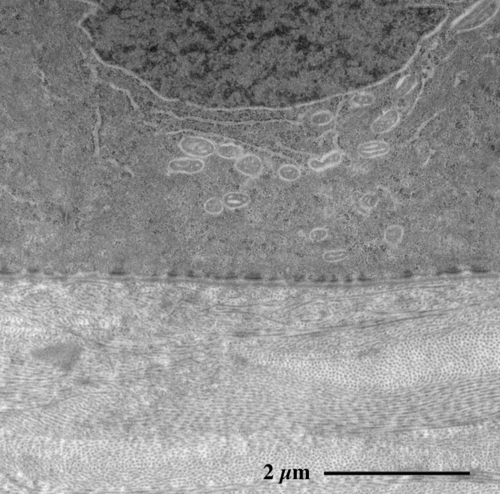

【 薄さ70 - 80 nm 超薄切片の透過型電子顕微鏡画像 】

Transmission electron microscopic image of 70 - 80 nm ultrathin section

角膜上皮層基底部

角膜固有質 stroma で互いに直交する膠原線維の層状構造